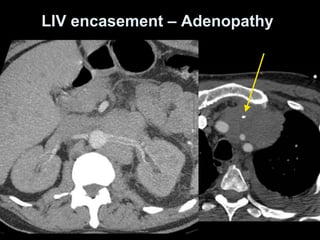

LIV encasement – Adenopathy

In-stent LIV / SVC thrombus

• 73.

IV cannula inleft arm. 100cc contrast + 20cc NS flush, diagnostic delay = 60sec. 60F ESRD, 3 overlapping stents placed for venous stenosis from previous catheters. Courtesy of Anne Chin, MD